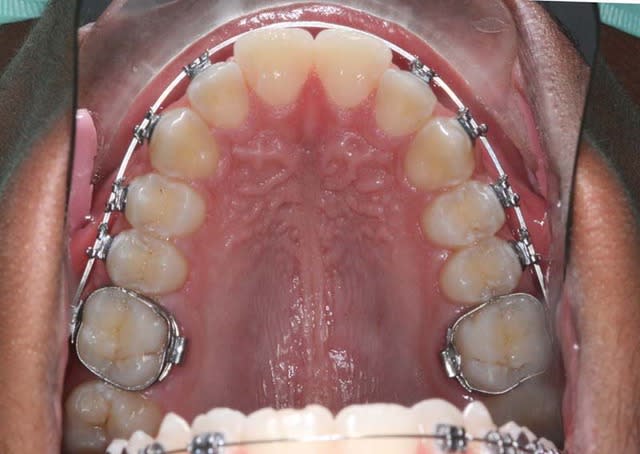

salut,

voici la mécanique mise en place pour ce cas et comment j’utilise (en friction faible, forces faibles) le fait que les Inc. Lat. soient bloquées en lingual pour le redressement des 3/4/5 tout en évitant la pro-version des Inc. centrales qui est Tjs. longue à rattraper et peut occasionner des rhizalyses

@+ Bjc.

mon arc (très peu puissant) est bloqué en 14, un peu en 12 et en 22

+ l’action du Q.H.

+ l’action de la lèvre Sup.

tu n’es pas obligé de croire, donc voici le résultat,

je viens de placer un arc 16*x16* austénitique, toujours pas inclus 11/21,

je vais d’abord appareiller le bas (sans inclure les 6) à la rentrée. pour encore laisser rentrer les centrales Sup. sous la pression de la levre

si on met des Bk. sur 11/21 on active (cintrage) l’arc en Ant. on n’aura pas d’action en Post. à part le Q.H. et les forces labiales seront trop faibles pour empêcher la version

le but est: ne pas verser les centrales tout en travaillant l’expansion qui fera de la place pour les reculer

quand on met 2 arcs, il y en a un actif et l’autre qui contrôle en se faisant aider par les forces musculaires sur l’ancrage

dans ce cas, on ne peut pas mettre d’arc de contrôle, on n’as pas l’ancrage 12/11/21/22 car 12/11/21/22 n’est pas aligné

si on mettait un 2° arc, il serait également actif, (on aurait l’équivalent d’un 20*x20*), tout exploserait, je n’ose imaginer les dégâts